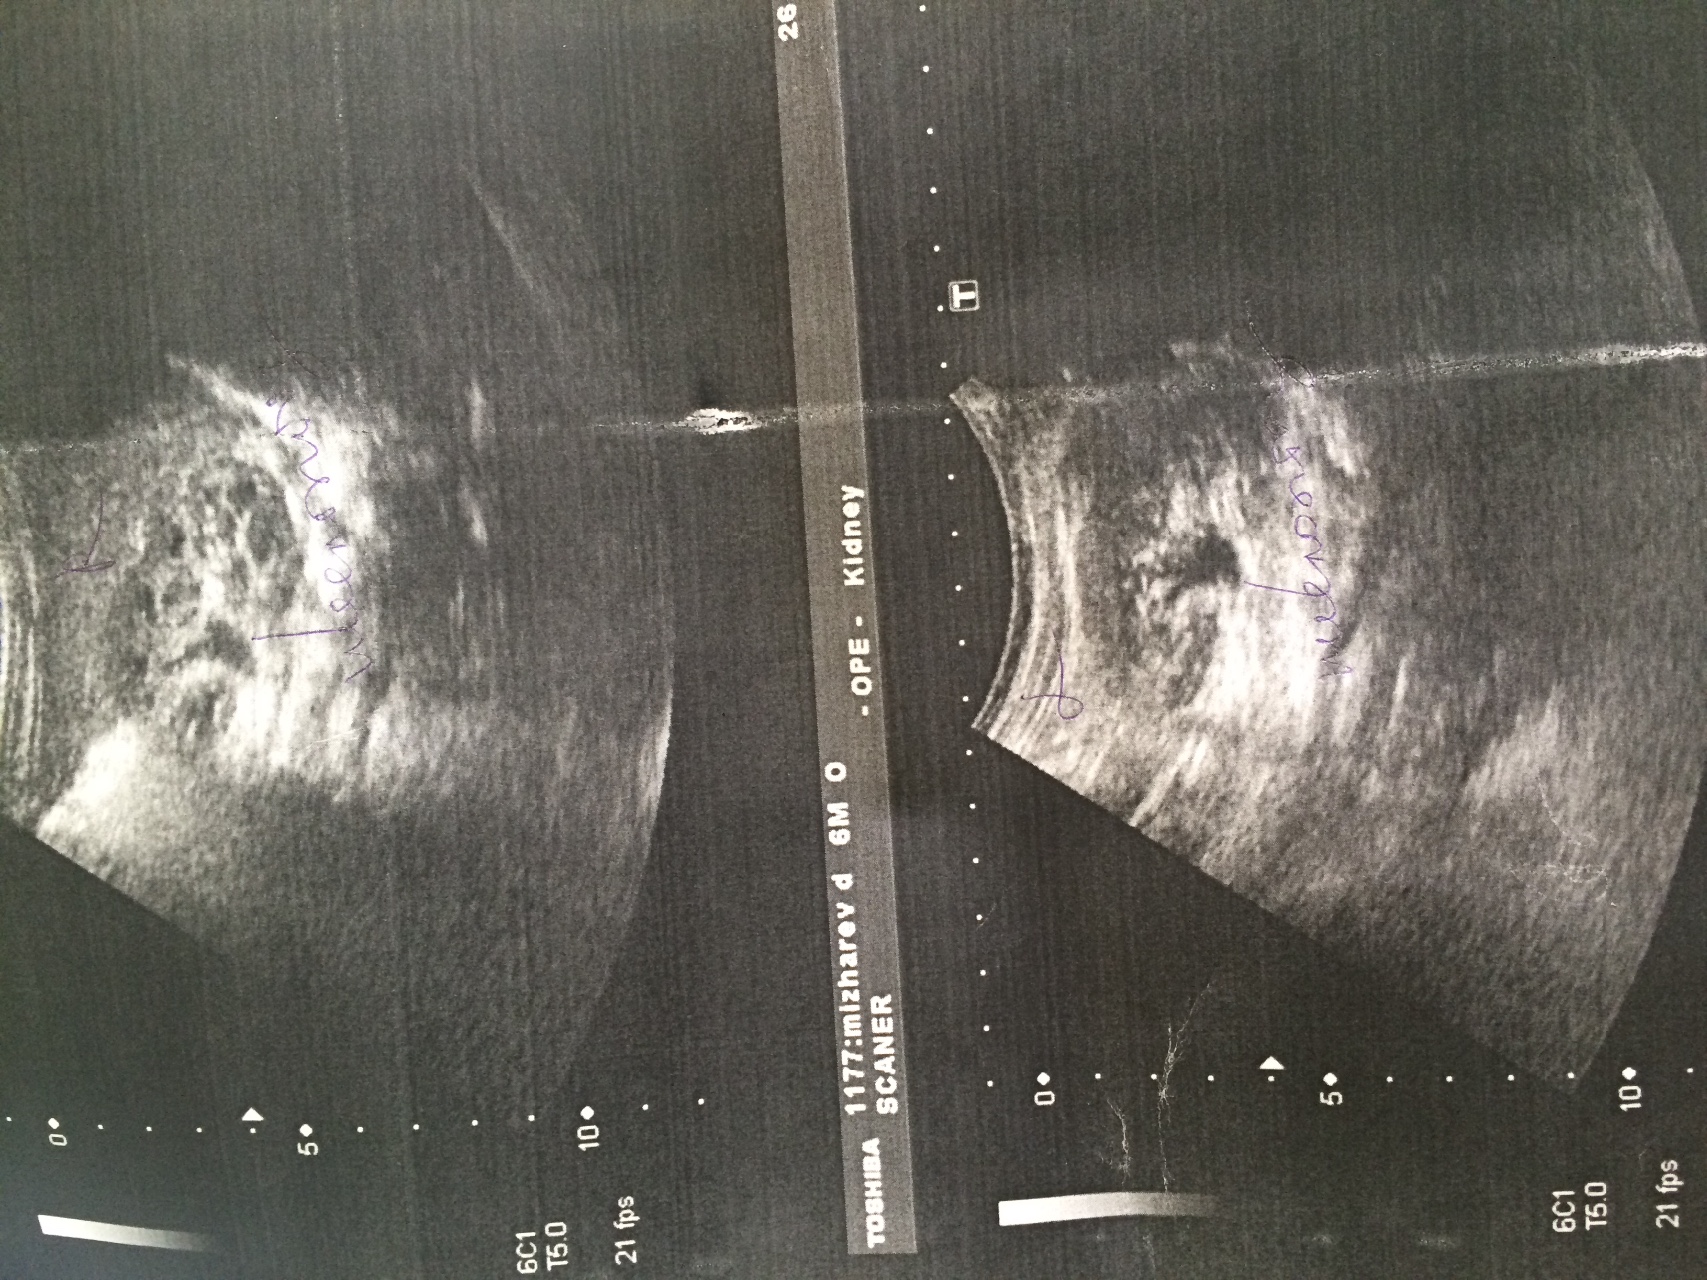

Интраренальная лоханка: рентгеновские снимки и примеры

Раздел: Фотоэссе